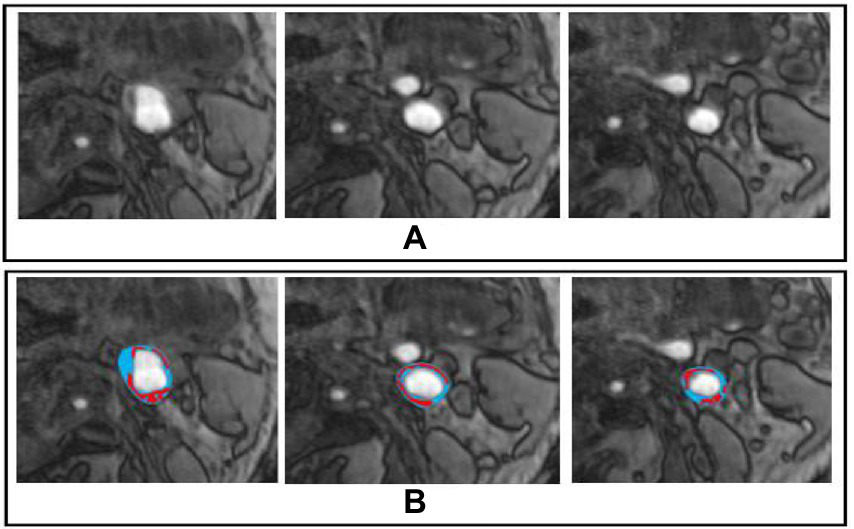

The sample dataset is shown in Figure 2. Furthermore, we also show the dataset statistics in the table for better understanding as shown in Table 1.

Figure 2

Sample Dataset, whereby (A,B) represents the original and marked image for carotid plaque, respectively.